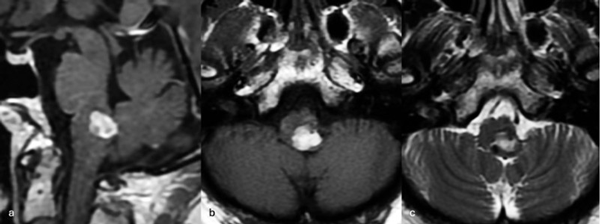

Una paciente femenina de 28 años, sin antecedentes de sangrado previo, debutó con cefalea, náuseas y vómitos, asociado a diplopía secundaria a una parálisis del VI par derecho. La RM de encéfalo evidenció una malformación cavernomatosa centrada en puente y el pedúnculo cerebeloso medio derecho (Figura 3). Un mes después del sangrado, se realizó una exéresis de la lesión mediante un abordaje retrosigmoideo ampliado a través del pedúnculo cerebeloso medio (Figura 4), logrando una exéresis completa (Figura 5). Tras el procedimiento, la paciente evolucionó con hemihipoestesia del hemicuerpo izquierdo, sin otros síntomas agregados.

Figura 3. RM preoperatoria de encéfalo. Se evidencia una lesión única intraaxial centrada en puente y pedúnculo cerebeloso derecho, sugerente de un cavernoma roto. A, B y C) Imágenes ponderadas en T2 en cortes sagital, axial y coronal, respectivamente, donde se observa un importante hiperintensidad perilesional, sugerente de edema.